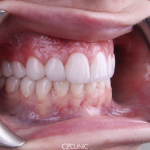

Состояние десневого края

Для эстетической целостности важно, чтобы десневые края были симметричны и находились в правильном положении перед проведением эстетических процедур. Уровни десен можно привести в идеальное положение с помощью лазера или скальпеля